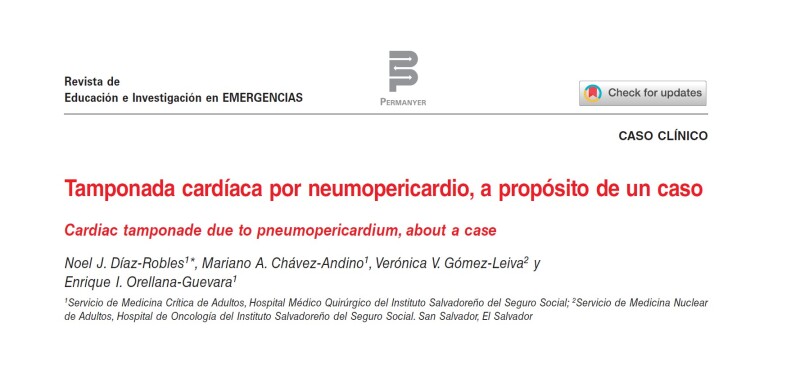

Especialidades De Medicina > Med Critica Y Cuidados Intensivos

Especialidades De Medicina > Med Critica Y Cuidados Intensivos

Especialidades De Medicina > Med Critica Y Cuidados Intensivos